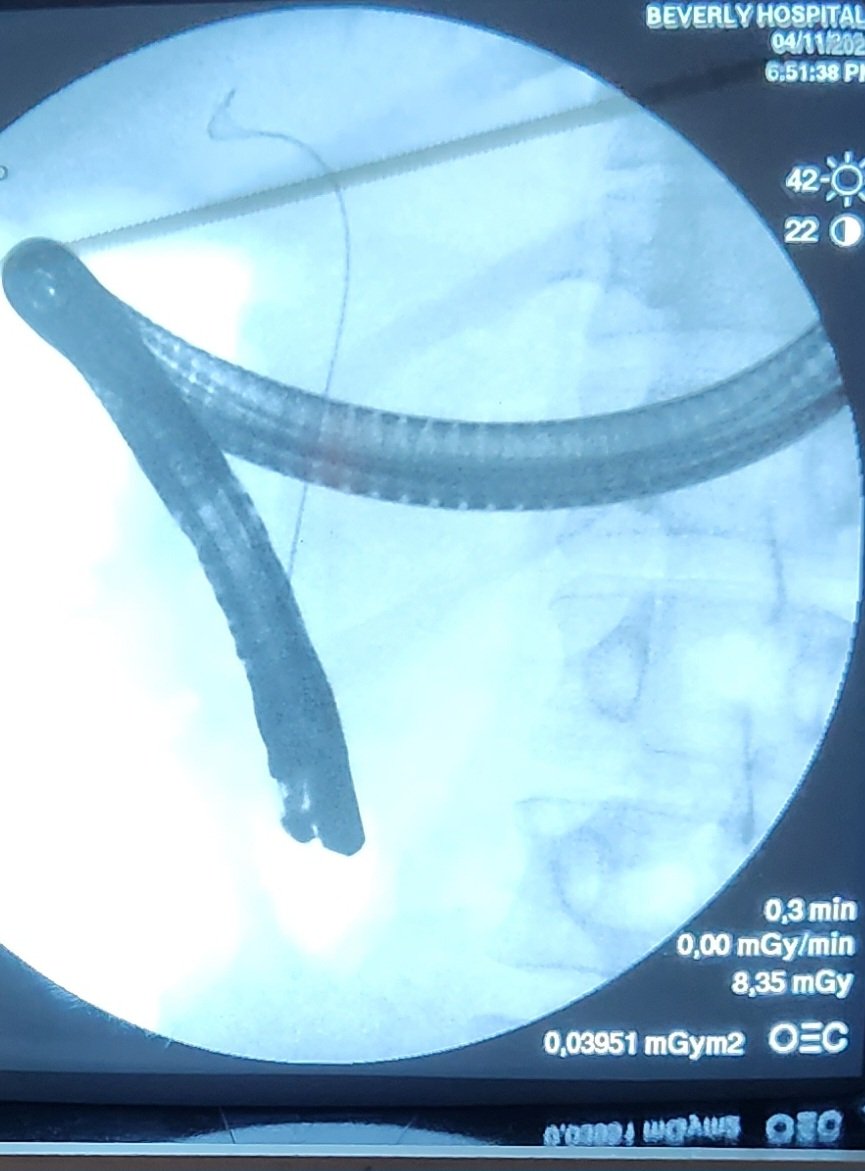

🔴Sphincteroplasty upto 15mm is good strategy to achieve full ductal clearance.This case referred for spyglass;CRE Dilatation 12mm successfully made the duct cleaned. @Almotasembilla1 @AlmuhaidbAymen @CarlKayMD @SyedGerdezi @DrSalihTokmak @drkeithsiau #ERC #Teaching #Cholangitis

Taalamri's tweet image. 🔴Sphincteroplasty upto 15mm is good strategy to achieve full ductal clearance.This case referred for spyglass;CRE Dilatation 12mm successfully made the duct cleaned.